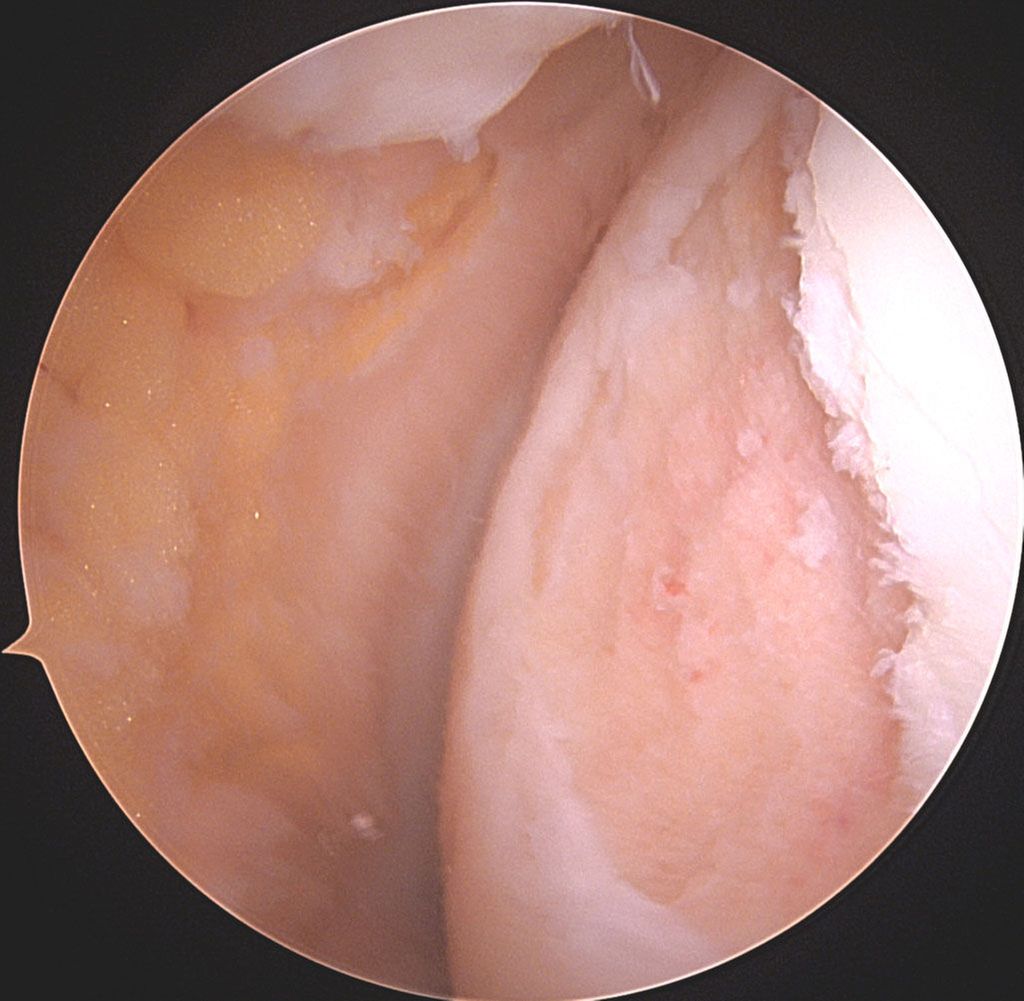

Abb. 1a und b: MRI-Bildgebung präoperativ bei grossem, vollflächigem Knorpelschaden an der medialen Femurkondyle einer jungen Patientin

Abb. 1c: Intraoperatives arthroskopisches Bild des Knorpeldefektes nach Debridement an der medialen Femurkondyle Knie links, Defekt 2 x 3cm = 6cm2